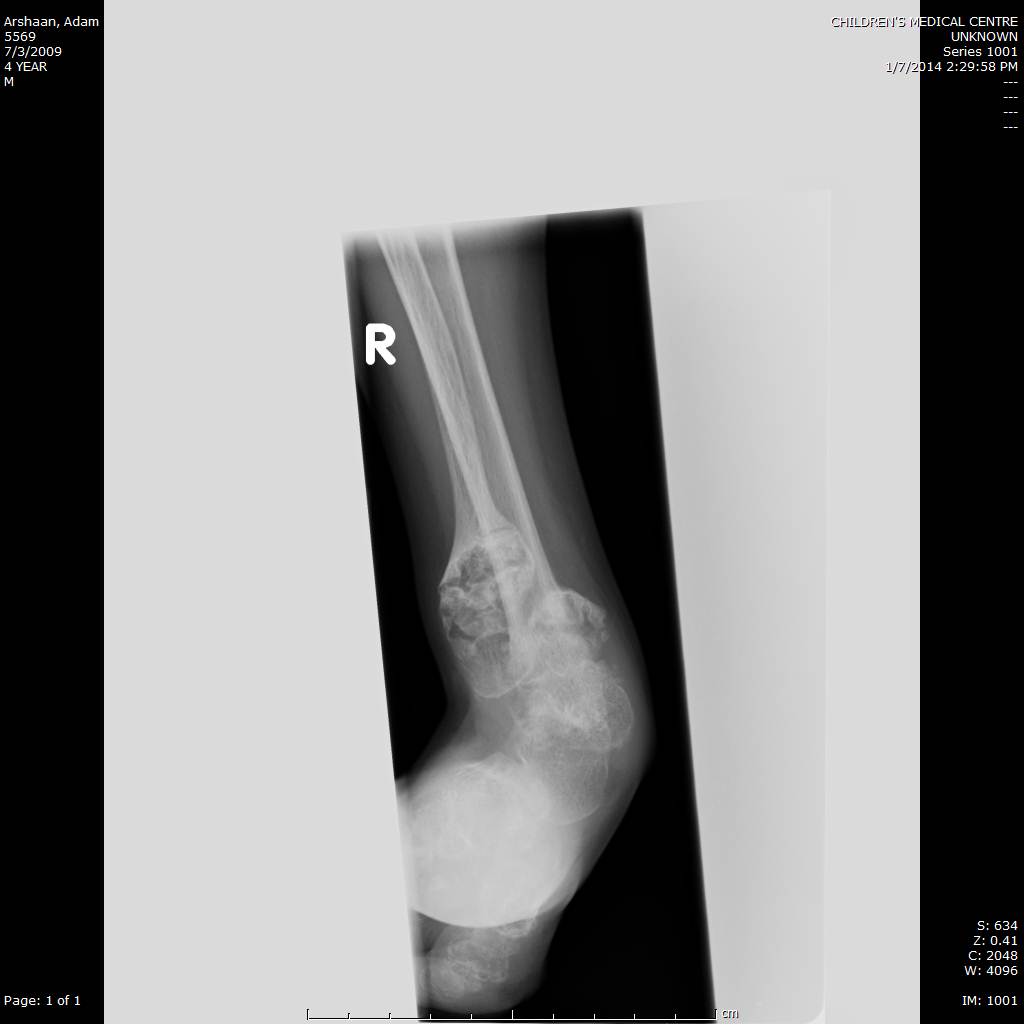

Here we share radiographic images to help with diagnosis of Jansen's disease:

Jansen's patients show extreme disorganization of the metaphyses of the long bones and of the metacarpal and metatarsal bones in sharp contrast to the almost normal appearance of the epiphyseal centers, which on x-ray appear widely separated from the long bones. The chin is receding. The fingers, especially the distal phalanges, are very short. The spine, pelvis, and lower legs are distorted.